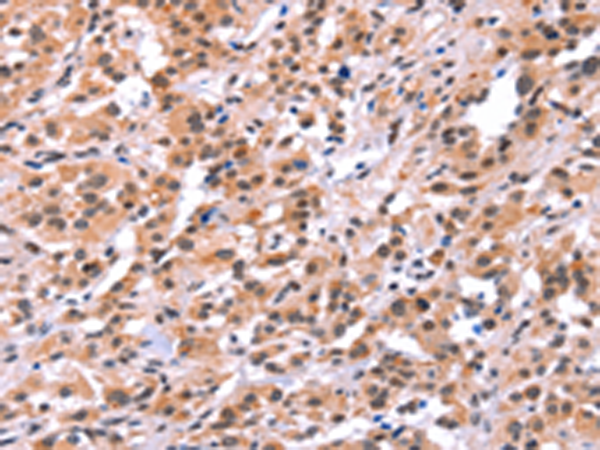

分类: 科研抗体货号: P04117别名: MMP25; MMP-24; MT5MMP; MTMMP5; MT-MMP5; MT5-MMP; MT-MMP 5应用: IHC反应种属: Human, Mouse, Rat